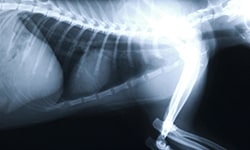

Eric Griesshaber provides animal wellness and emergency services for pet owners in the Silicon Valley.

I’m pleased to share that I am now part of the team at West Valley Pet Clinic, where I continue to provide veterinary care with the same dedication and compassion.

Eric Griesshaber, D.V.M. / Veterinarian Cupertino CA